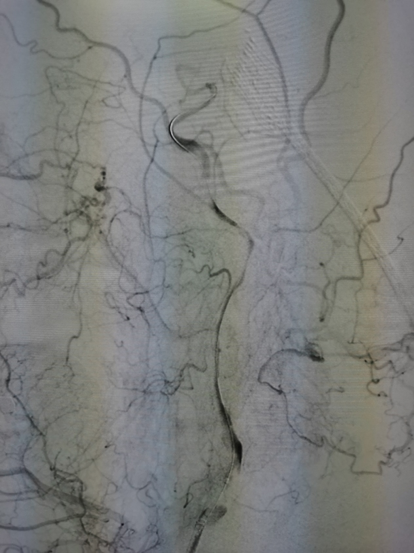

图4 TOF像显示岩骨段慢血流

图5 眼段可见正常管腔,血管负性重构

图6 M1段血管存在